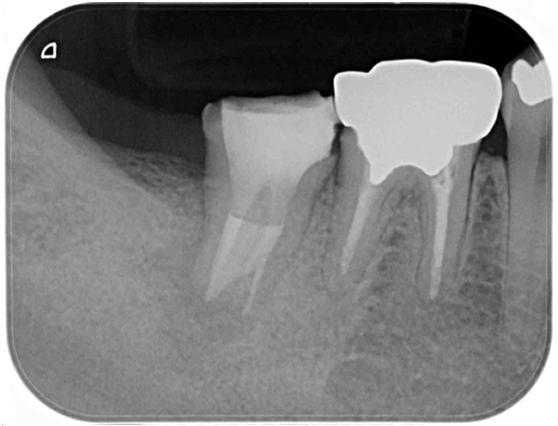

根管治療 症例 2

詳しく見る